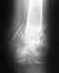

Диагноз: Закрытий оскольчатый перелом диафиза правой плечевой кости со смещением. 31.07.14 выполнено оперативное вмешательство - закрытая репозиция, БИОС правой плечевой кости (Deost L=240мм d=9мм)

Диагноз: Закрытий оскольчатый перелом диафиза правой плечевой кости со смещением. 31.07.14 выполнено оперативное вмешательство - закрытая репозиция, БИОС правой плечевой кости (Deost L=240мм d=9мм) Необходимость задать вопрос возникла из-за взаимоисключающих рекомендациях в лечении двух травматологов (врач оперировавший г. Сочи, врач наблюдающий г. Норильск) свести вместе я их не могу так как города разные. Вопрос: - врач Норильск, когда сделал снимки (23 08 14) сказал срочно иммобилизовать руку и одел на меня ДЕЗО. - врач Сочи говорит (пишет), что необходимо выполнять "Активные движения (без нагрузок) в локтевом и плечевом суставе", т. е. Работать рукой по минимуму, иммобилизацию руки считает "крайней степени неграмотность в данном случае". 1. Иммобилизовать руку или нет? 2. Можно ли двигать рукой или нет? 3. Как будут сращиваться кости если они друг с другом не сопоставлены (на снимках видно)? 4. Ориентировочный срок сращивания? - при иммобилизации? - при активных движениях? 5. Подвижны ли кости (отломки) сейчас в правой руке или статичны? 6. Как я понимаю они (кости как на снимке) в таком положении срастаться и будут, т. е. У меня будет шишка на плече? (в месте где кость отступает от штифта, я её чувствую (шишку) когда ощупываю руку). И как я понимаю форма кости после восстановления будет очень фигурная (а не ровная)? 7. При таком виде перелома и виде остеосинтеза, восстановление функции руки будет 100%? 8. Нормально ли, что я не могу отвести руку (чувствуются болевые ощущения) от себя сбоку более чем на 45 градусов в плечевом суставе? Спасибо:

Покажите нормального качества свежие ренгенограммы.